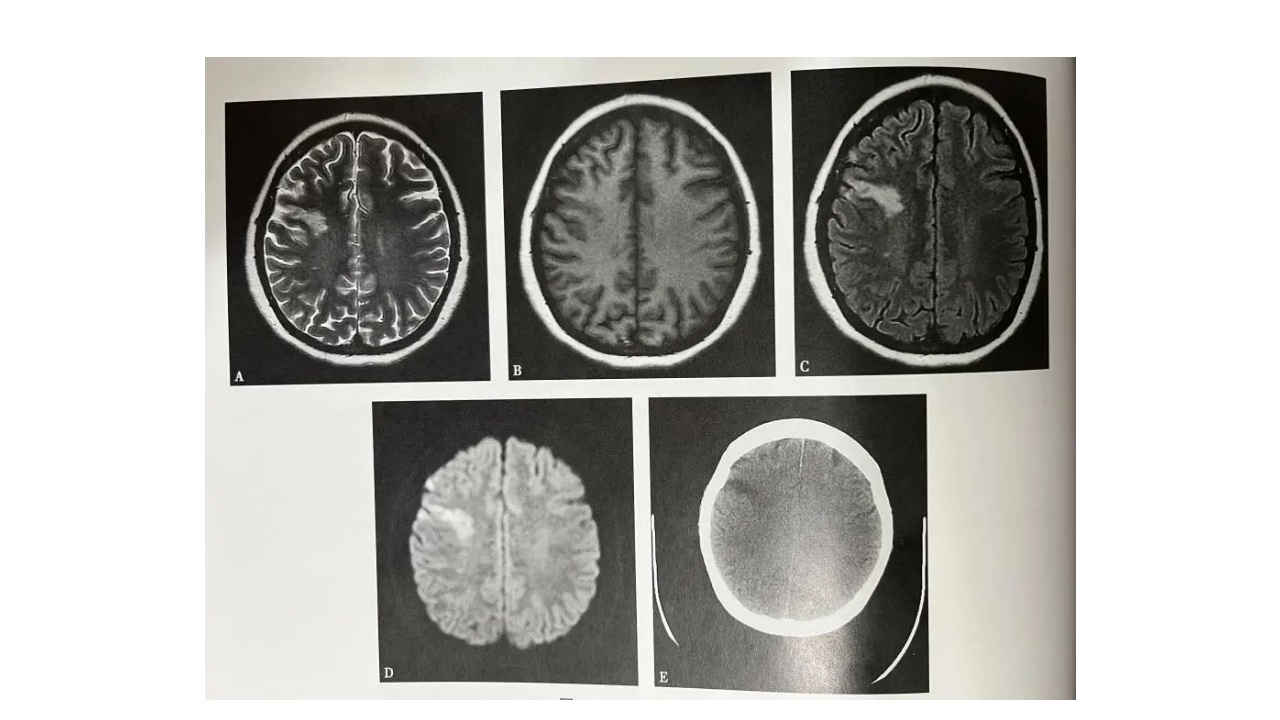

图3:分水岭脑梗死

图4.左侧额叶静脉性脑梗死男,24岁,头痛5天,发作性肢体抽搐、意识丧失2天。A~D(A.T2WI,B.T1WI,C.T2WI-FLAIR,D.DWI):左侧顶叶可见片状长T1长T2信号灶,内部可见条状短T1短T2信号灶。E.MRV,上矢状窦部分未见显影